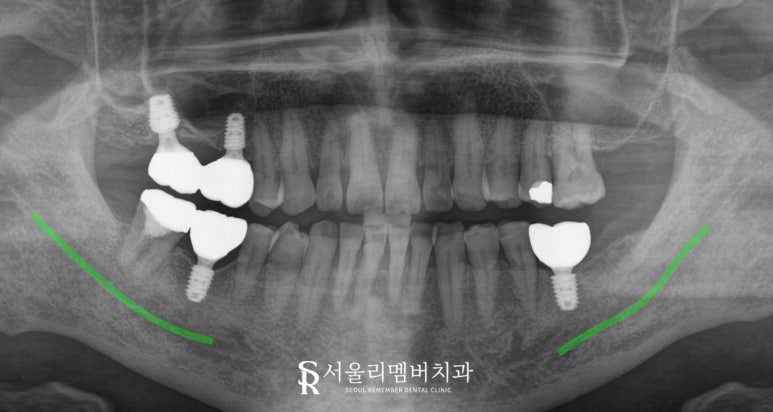

치료 과정: 안전하고 꼼꼼하게 진행

먼저 16번과 17번 부위에

거상술과 뼈이식을 통해 부족한 치조골을 보강한 후

임플란트를 식립했습니다.

하악 46번과 36번도 하치조신경과의 거리를

신중히 계산해 안전하게 임플란트를 완료했습니다.

47번은 낙성대 치과 에서

크라운 수복을 통해 기능을 회복했습니다.